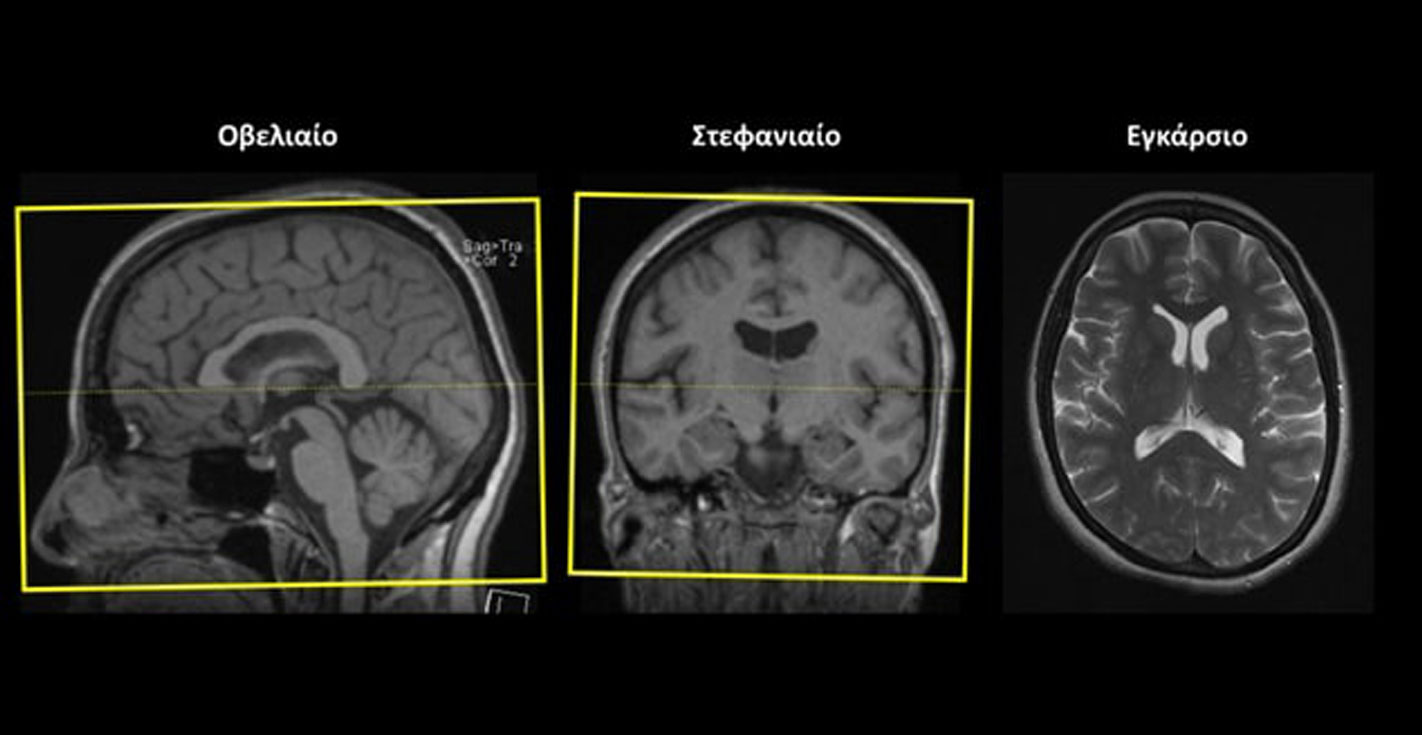

Εγκάρσιο (Axial/Transversal) ολόκληρου του εγκεφάλου: οι εγκάρσιες τομές σχεδιάζονται παράλληλα με το πρόσθιο (γόνυ) και το οπίσθιο (σπληνίο) κέρας του μεσολοβίουστο οβελιαίο επίπεδο και κάθετα στη μέση γραμμή του εγκεφάλου στο στεφανιαίο επίπεδο. Οι τομές πρέπει να περιλαμβάνουν ολόκληρο τον εγκέφαλο έως και την παρεγκεφαλίδα (κάτω).

Στεφανιαίο (Coronal): οι στεφανιαίες τομές σχεδιάζονται παράλληλα με τους φακούς των οφθαλμών στο εγκάρσιο επίπεδο και κάθετα στα οπτικά νεύρα στο οβελιαίο επίπεδο. Κάποιες φορές το οπτικό νεύρο του δεξιού οφθαλμικού κόγχου έχει διαφορετική κλίση από το οπτικό νεύρο του αριστερού οφθαλμικού κόγχου στο οβελιαίο επίπεδο. Σε αυτή την περίπτωση, οι στεφανιαίες τομές σχεδιάζονται κάθετα στο οπτικό νεύρο του οφθαλμικού κόγχου ενδιαφέροντος. Οι τομές πρέπει να περιλαμβάνουν ολόκληρη την περιοχή ενδιαφέροντος, από τους φακούς των οφθαλμών (μπροστά) έως και το οπτικό χίασμα (πίσω). Tip:Το οπτικό χίασμα βρίσκεται στο ίδιο ύψος με την υπόφυση.

Εγκάρσιο (Axial/Transversal): οι εγκάρσιες τομές σχεδιάζονται παράλληλα με τη νοητή γραμμή που ενώνει τα δύο οπτικά νεύρα στο στεφανιαίο επίπεδο και παράλληλα με τα οπτικά νεύρα στο οβελιαίο επίπεδο. Κάποιες φορές το οπτικό νεύρο του δεξιού οφθαλμικού κόγχου έχει διαφορετική κλίση από το οπτικό νεύρο του αριστερού οφθαλμικού κόγχου στο οβελιαίο επίπεδο. Σε αυτή την περίπτωση, οι εγκάρσιες τομές σχεδιάζονται παράλληλα με το οπτικό νεύρο του οφθαλμικού κόγχου ενδιαφέροντος. Οι τομές πρέπει να περιλαμβάνουν ολόκληρη την περιοχή των οφθαλμικών κόγχων, από πάνω έως κάτω.